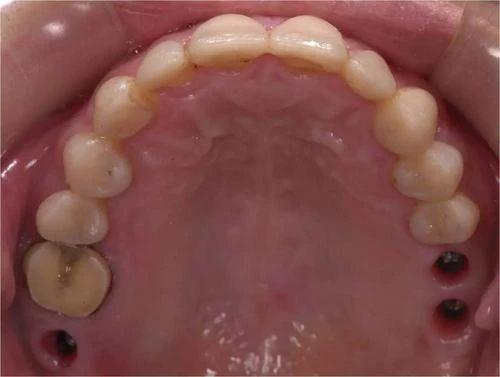

1、造成牙本质暴露的原因很多,最常见的是牙齿过度磨损。龋病侵犯到牙本质时也会产生酸痛。但不是所有的牙本质暴露部位都会产生酸痛,牙酸的发生还与牙本质内细小管道与牙髓神经末梢的敏感性或传导性有关。

2、一些脱敏牙膏使用较方便,适合症状较轻者用。如果病因是龋坏,则需去除病变组织,用材料“补牙”。如果牙本质暴露的面积太大或药物涂擦法效果不佳则应作牙冠覆盖牙齿,以保护牙齿。坚持早晚刷牙,坚持温水刷牙,坚持吃水果或者任何东西后刷牙。可以减轻或者控制牙齿发酸。

4、补牙后牙齿酸软是一个正常的术后反应,特别是龋坏较深的情况下,一般观察一段时间后酸软症状会消失,根据个体差异一般需观察2周到2月时间不等。你好,这种情况是在做根管治疗,积极配合医生治疗。避免咬食硬物。 建议多喝水,饮食以清淡好消化为主,禁食辛辣食品,补牙后近期避免咬食硬物。多观察。如果酸软症状仍不消失甚至出现疼痛不适此时可能需要行根管治疗术。

5、补牙材料能保持多久?补牙后牙齿的使用时间与补牙的材料选择有着密切的联系。牙洞如果较大、较深且形状不规则,或是邻面牙洞,则充填好的牙齿就应小心使用。否则,咬硬物时易出现牙齿劈裂或充填物脱落。补牙后牙齿的使用时间与日常的口腔保护有关,如平时多注意口腔的清洁,以及养成良好的用牙习惯,那么补牙后的牙齿可以是终身的。